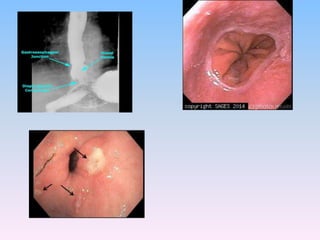

INVESTIGATIONS:

• IOC: CT thorax with upper abdomen (oral

contrast)

• Others:

• Barium oesophagogram

• Upper GI endoscopy

• Manometry

• Ambulatory pH monitoring

INVESTIGATIONS: • IOC: CTthorax with upper abdomen (oral contrast) • Others: • Barium oesophagogram • Upper GI endoscopy • Manometry • Ambulatory pH monitoring